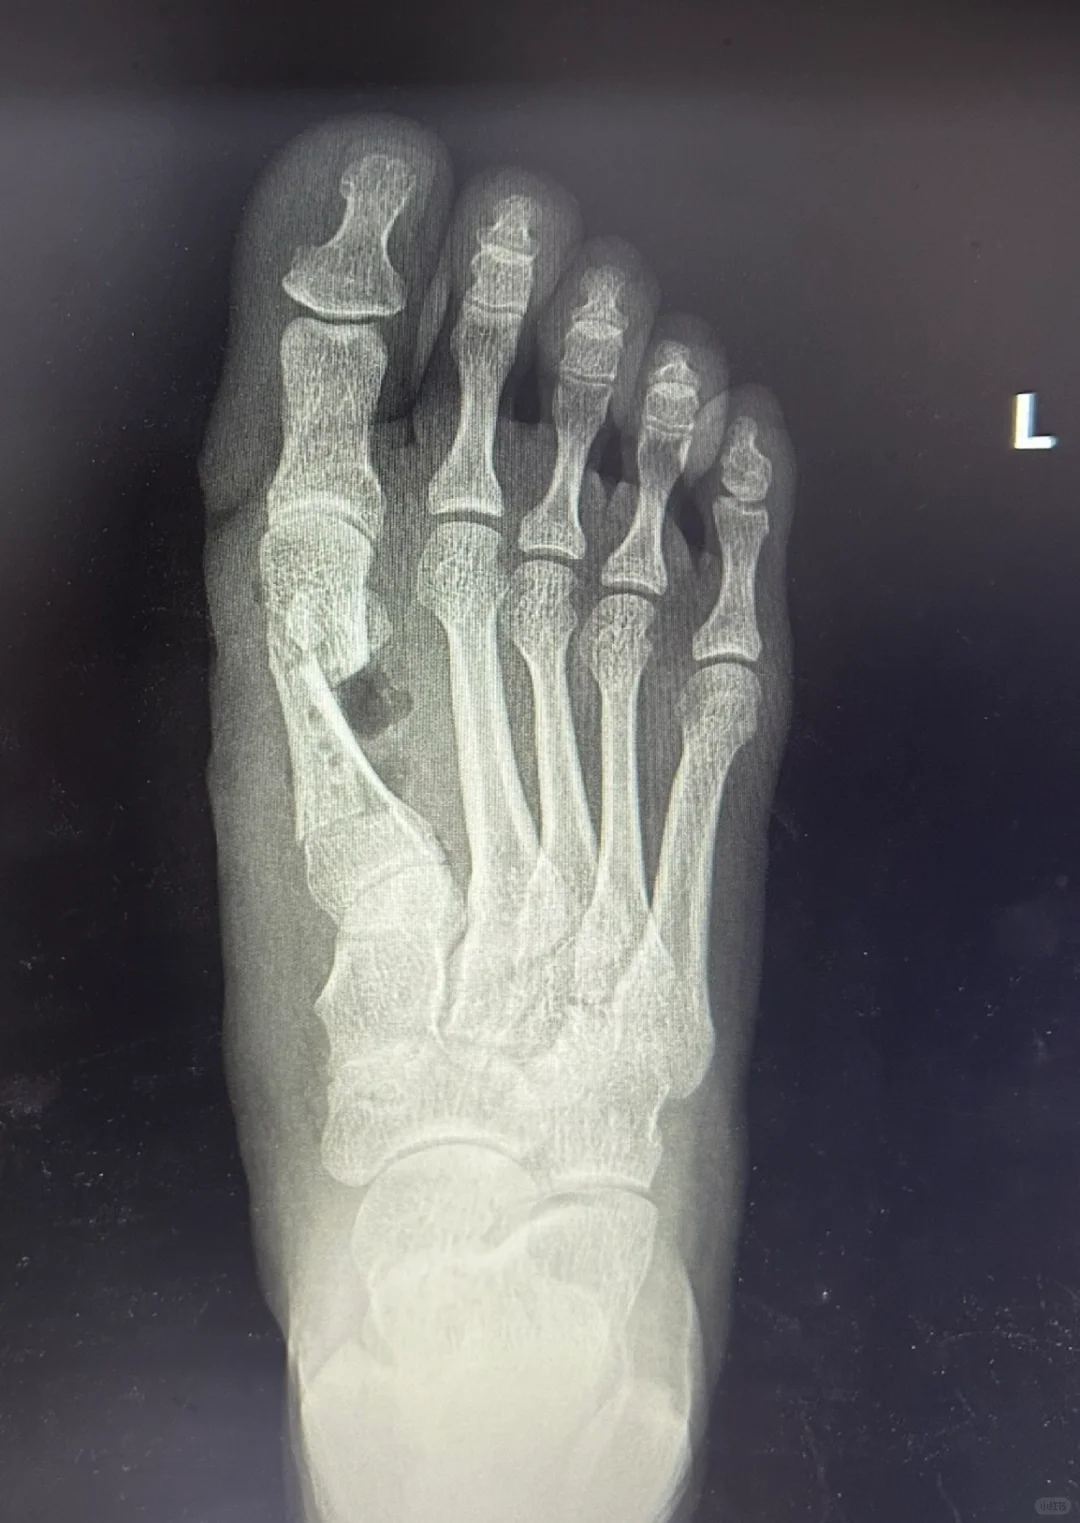

第三种,看片子

手术后就直接一步到位,所有的骨关节和软组织都处理好了,1.2趾的间隙与正常人一样。

你还要夹卷吗?绷带都不需要用,1.2趾无间隙。你的任务就是等待愈合。